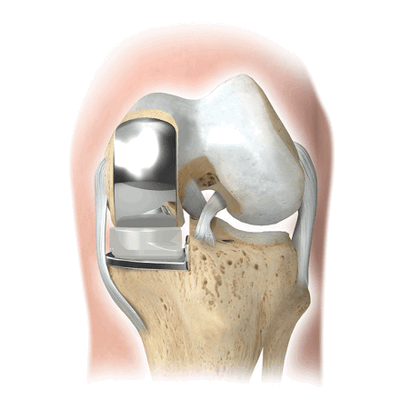

Сама операция выполняется с определенной этапностью:

- Сначала делается антисептическая обработка области сустава, затем нога покрывается пленкой.

- Хирург делает небольшой (до 10 см) разрез мягких тканей через переднюю поверхность и аккуратно обнажает поврежденный сустав.

- Удаляют патологические хрящевые и костные зоны.

- Затем структурные компоненты выстраиваются по оси, снимаются верхние слои бедренных и большеберцовых костей, опиленные компоненты подвергаются шлифовке.

- В большеберцовой кости делается небольшой канал, куда устанавливается задняя втулка протеза.

- На бедренную кость устанавливается другая часть протеза, сходная со структурой удаленной части кости бедра.

- В конце операции рану промывают, делается гемостаз, проводится дренаж раны. Разрез ушивается при помощи узлового шва. Завершается процесс наложением тугой стерильной повязки на прооперированную область.

Упрощенная схема установки импланта.